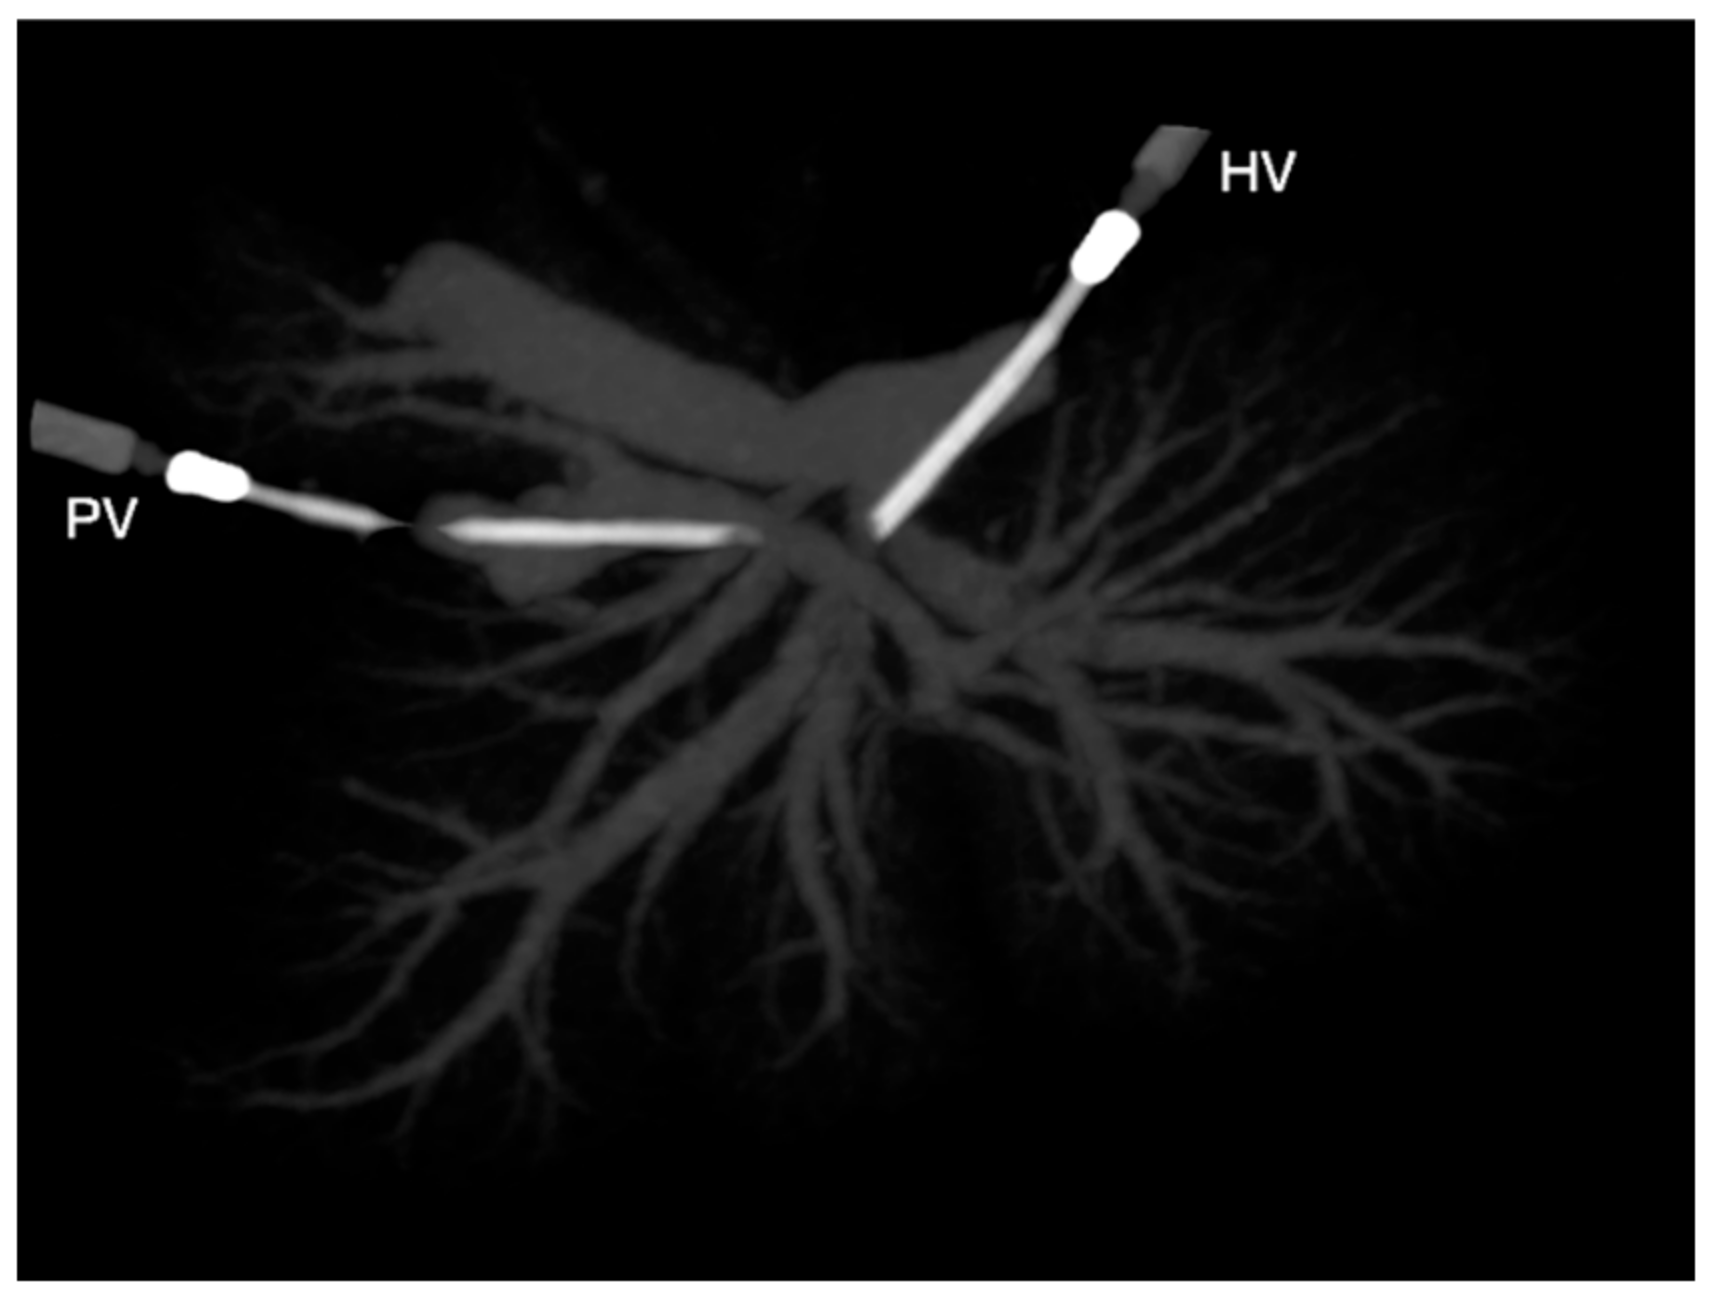

Figure 2.

Ventrodorsal view on a maximum-intensity projection (MIP) of a liver cast. HV, catheter to the hepatic vein; PV, catheter to the portal vein.

CT scans of the livers with the resin casts were performed the day following casting using a helical scan technique with a 1 mm slice thickness, 0.5 mm increment, 120 kV, and 140 mAs (Brilliance CT 16 slice; Philips Medical Systems, Eindhoven, the Netherlands). The livers were scanned in the same saline-filled containers to ease the distinction between the liver lobes in the scans. The acquired images were reconstructed using a bone and soft tissue algorithm before being stored in the PACS system (IMPAXEEServer_Rad, Agfa HealthCare, Mortsel, Belgium). The scans were analyzed as multiplanar reconstructed images using a DICOM reader (DeepUnity R20 XX, DH Healthcare GmbH, Bonn, Germany) to evaluate the number and location of the vascular branches of the intrahepatic PV and hepatic veins. Primary branches were defined as venous branches arising directly from the PV or joining the post-hepatic CdVC, while secondary branches were the further veins that ramified inside one lobe from the primary branches. Tertiary branches were defined as further ramifications of secondary branches within one single liver lobe. In addition, their relationships with different lobes were recorded. Three-dimensional volume-rendered images and maximum intensity projections were produced to allow easy comparison of the liver vasculature (Figure 2). The livers were macerated using an enzymatic solution (Biozym SE; Spinnrad GmbH, Bad Segeberg, Germany) at 60 °C for approximately 36 h. The remaining parenchyma was removed via gentle rinsing with water. The tertiary and smaller branches of the veins were manually removed, allowing a better macroscopic view of the main branches of the different venous systems.